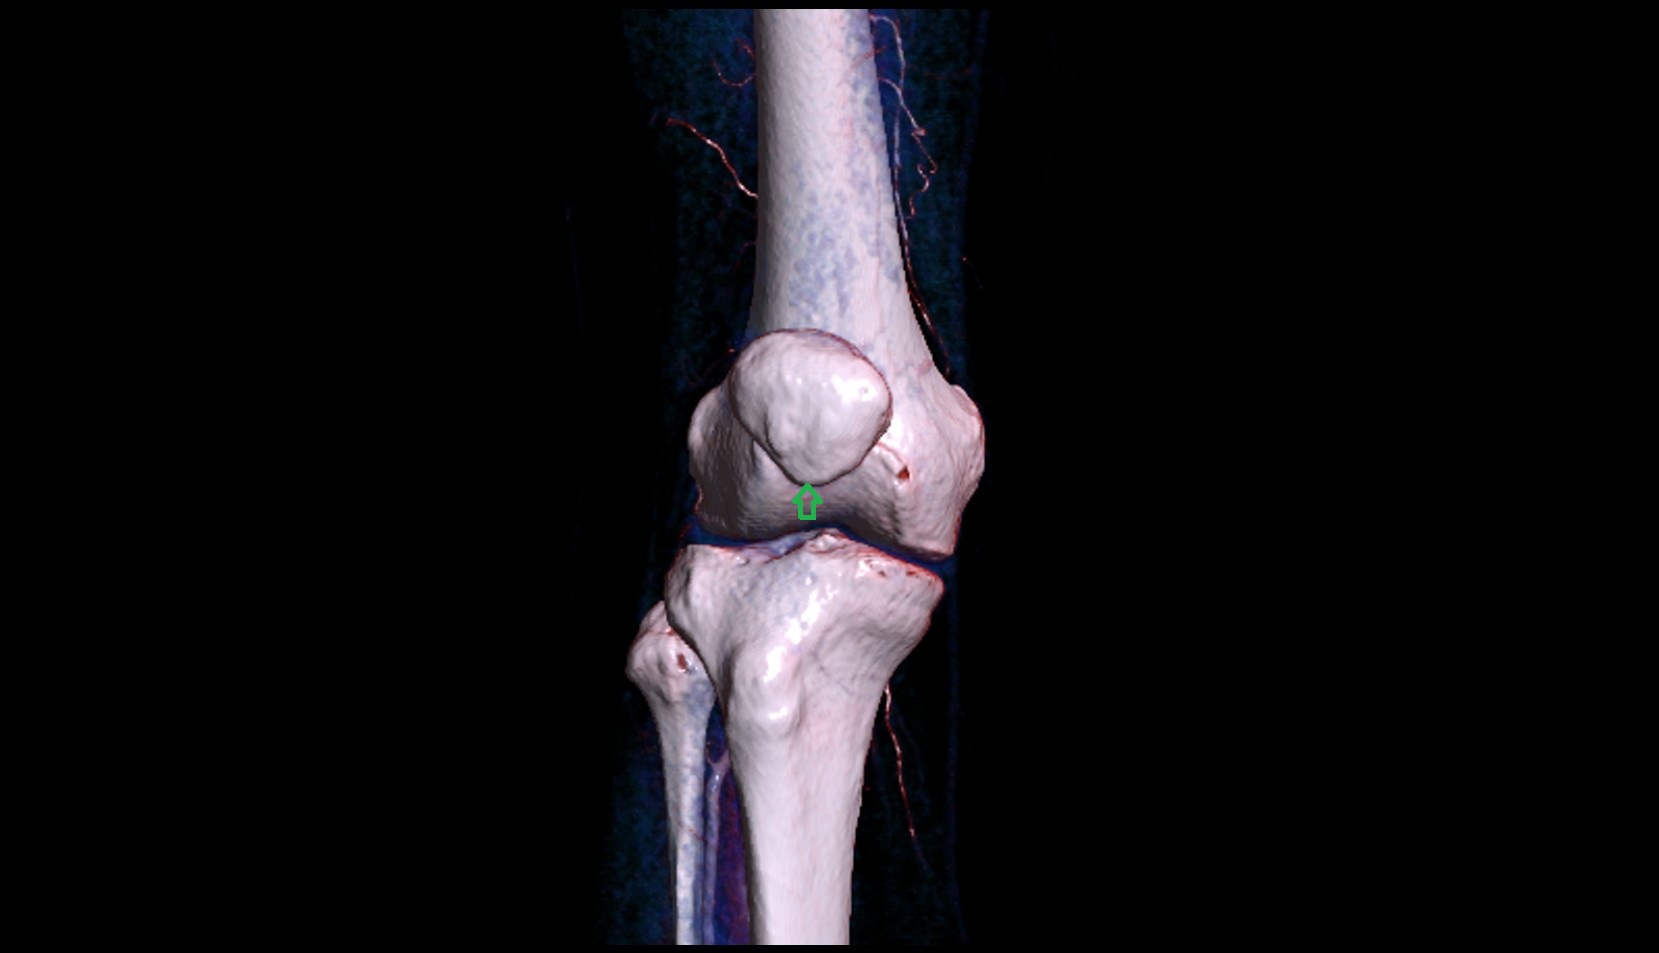

- Knee Joint